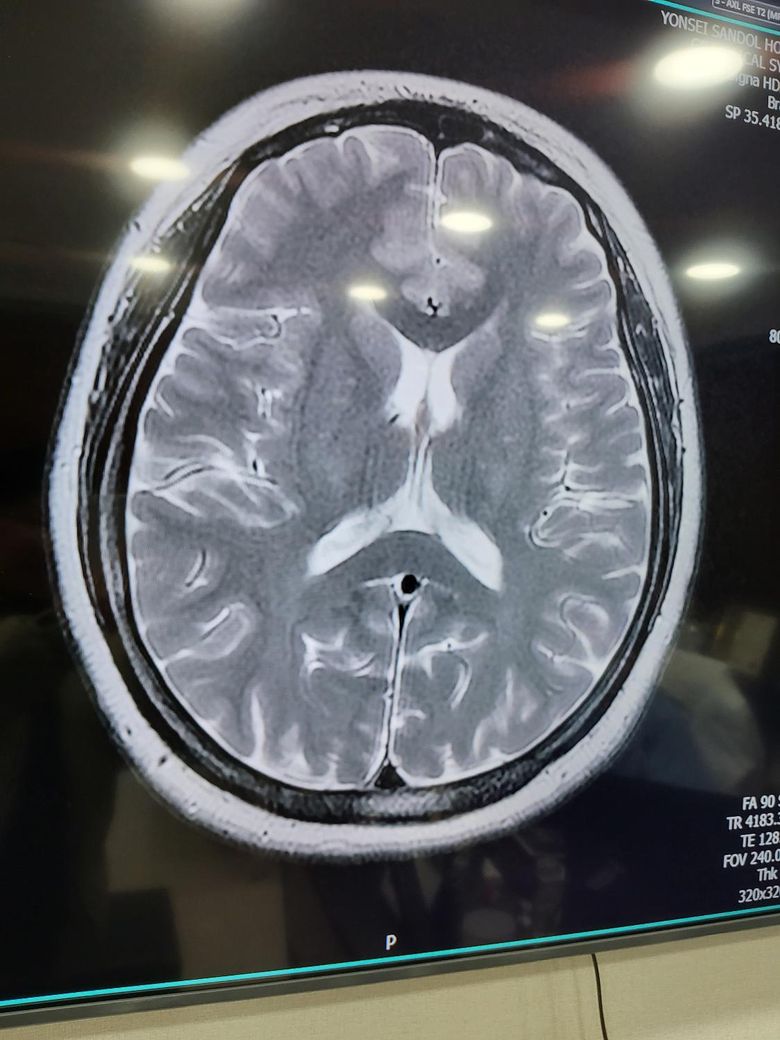

뇌 mri검사 교량 다른사람들보다 좁아 질문

두통,어지러움때문에 뇌 mri검사를 받았는데 다른 사람보다 뇌 교량이 좁다고 했는데. 따로 치료 안받아도되나요?? 어렸을때 간질이나 경련 없었으면 그냥 얼굴형이 다른것처럼 다르게 생긴거라고 하는데 어렸을때 그런 증상이 없으면 안심하고 지내도 되나요??아니면 추적검사를해야하나요?? 뇌교량이 두통하고 어지러움 연관이있나요??

• 3번 째 사진